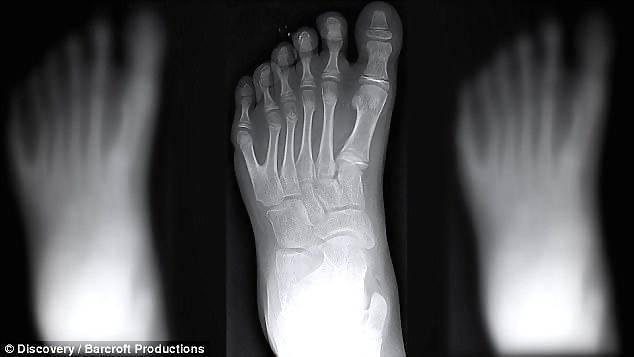

对于大多数父母来说,都不愿意听到自己的孩子患有残疾的消息。 但来自巴西的达席尔瓦家族却不这么认为,他们自豪地发现,他们的家族中有14名成员都有6个手指和脚趾。